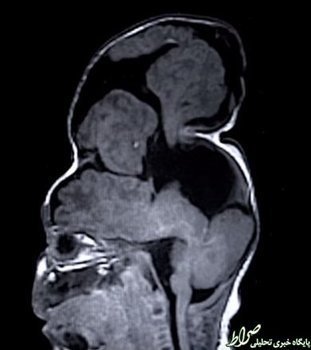

پزشکان کلینیک کلیولند اوهایو طی انجام یک عمل جراحی فوق العاده دشوار و خطرناک موفق شدند مغز یک کودک را که در خارج از جمجمه شکل گرفته بود به حالت طبیعی برگردانند.

به گزارش ایسنا به نقل از گیزمودو، این کودک که بنتلی نام دارد مبتلا به یک بیماری نادر به نام آنسفالوسل یا بیفیدوباکتریوم جمجمه بود که مشکلش در هفته 22 بارداری مادر و با انجام سونوگرافی تشخیص داده شد.

انسفالوسل (encephalocele) نوعی بیماری مادرزادی است که به سبب تشکیل ناقص سلول‌های عصبی جنین بروز می‌کند.

در این بیماری بخش‌هایی از مغز به صورت برآمدگی، از طریق روزنه‌های جمجمه بیرون زده و پوست و یا غشاء نازکی روی آن را می‌پوشاند.

جراحان پس از بررسی وضعیت این کودک دریافتند که بخش‌هایی از مغز کودک که در خارج از جمجمه شکل گرفته و روی آن پوسته تشکیل شده، قابل حذف شدن نیست چرا که آنها مسئول عملکردهای شناختی مانند کنترل حرکت، حل مسئله و بینایی بودندبنابراین آنها راهکاری را برای حل این مشکل در نظر گرفتند.

پزشکان برای انجام این عمل جراحی از مدل‌های چاپ سه بعدی استفاده کردند. 100 سانتی متر مکعب از مغز بنتلی خارج از جمجمه وی شکل گرفته بود، به طوری که جراحان ناچار به  گسترش جمجمه او شدند. آنها قبل از انجام این عمل جراحی از یک مدل پلاستیکی استفاده کردند تا نتیجه این عمل را پیش بینی کنند و دریابند که چه میزان از مغز را می‌توان در جمجمه جای داد.